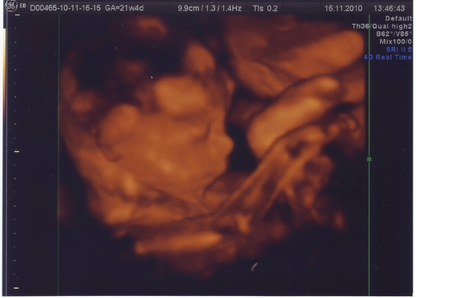

Второе плановое УЗИ.

Второе УЗИ уже делают через живот в отличие от первого. Наш малыш крепко спал, когда мы ворвались к нему своими любопытными взорами. :) Такой хорошенький, поджал ручку под щёчку и сладко дремал. Даже не проснулся. Хотя всегда реагирует, когда живот трогают. Сколько раз врачи приходили на осмотр в больнице, трогали живот, малыш твердо стоял за себя- давал сдачу! Даже зав.отделением однажды стукнул! :))

Однако, сон не помешал как следует рассмотреть нашего ребеночка и обследовать его. Сразу стало ясно, что у нас будет сыночек - пол подтвердился сразу. Наш сын оказался не из стеснительных! :) Все внутренние органы у малыша сформированы, все показатели соответствуют норме. Очень долго со всех сторон прослушивали сердечко, я так волновалась, но и сердечко наше не подкачало - здоровенькое! :)

Малыш уже перевернулся головкой вниз, обвития нет. Оказалось, что периодически малыш не ручкой стучится в мой живот, не ножкой пинается, а бодается! :))) Вообще сейчас каждый раз когда он шевелится, я уже представляю, где он ножкой меня пнул, где головкой боднулся, а где попкой вильнул. :)

Если на первом УЗИ мне поставили ПДР 22 марта, то на втором плановом УЗИ срок сместился на 23 марта. Врач сказал, что это очень хорошо, ведь это значит, что малыш развивается равномерно и полностью соответствует норме по всем показателям. Срок в срок! :) Нам было очень приятно слышать, что наши результаты настолько соответствуют норме :)